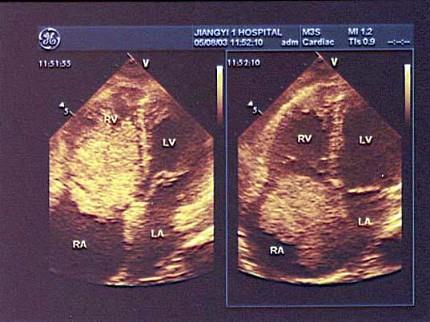

该病例最可能的诊断?(?)A.血栓B.房间隔膨胀瘤C.黏液瘤D.赘生物E.以上都不是

问题 该病例最可能的诊断?(?)

选项 A.血栓 B.房间隔膨胀瘤 C.黏液瘤 D.赘生物 E.以上都不是

答案 C